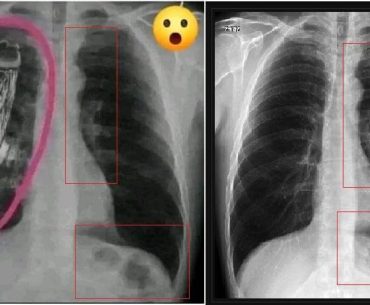

Sosyal medya platformlarında dolaşıma giren görsellerin bağlamından koparılarak yeniden kurgulanması ve sansasyonel hikayelerle servis edilmesi sıkça rastlanan bir durum. Özellikle sağlık sistemi, tıbbî ihmaller ve bürokratik yetersizlikler üzerine kurgulanan anlatılar, kullanıcıların duygusal tepkilerini tetikleyerek hızla yayılma eğilimi gösteriyor. Bu tür içeriklerin ilginç örneklerinden biri, Kenya’daki bir devlet hastanesinde çekildiği…